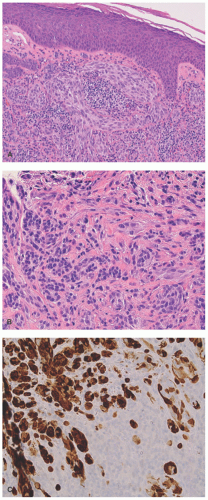

Atypical SN (Tumor)

Atypical Spitz nevus (tumor) (ASNT) in its simplest terms is a nevocellular lesion with the basic histopathologic features

of a SN, but with sufficient histopathologic variance to cause concern about the possibility of a melanoma with spitzoid features.97 It should be recalled that Spitz regarded all the lesions in her series as atypical to the degree that she considered them all “melanomas of childhood.”71 Another expression of the challenge of the SN is the reference to them as the “everlasting diagnostic challenge.”98 Mones and Ackerman99 considered ASNT as nothing more than an evasion from a straightforward diagnosis.

The following are some of the applied morphologic features of a ASNT: (1) lesions greater than 1 cm; (2) solid rather than nested growth pattern extending to the deep reticular dermis and into the subcutis with exceptions; (3) asymmetrical growth into dermis; and (4) cytologic atypia in the form of enlarged nuclei with pleomorphism and dense irregular chromatin.72,100 Nuclear atypia and its degree are subjective from one observer to another to account in part for the inter- and intraobserver variability. We have found it helpful to review the last “typical” SN and compare it to the current case where there is concern about an ASNT. Marked atypia is usually present throughout all levels of an ASNT, and mitotic figures, if present, should be counted with a threshold of greater or less than 6 mitoses per mm (Figure 22-18A and B).2 The emphasis on mitotic figures in the evaluation of any melanocytic lesion is usually focused upon those mitoses in the mid-to-deep reticular dermis. However, numerous mitotic figures wherever they are identified should be integrated into the overall assessment with the other histopathologic findings, which is the case in any nevocellular proliferation.